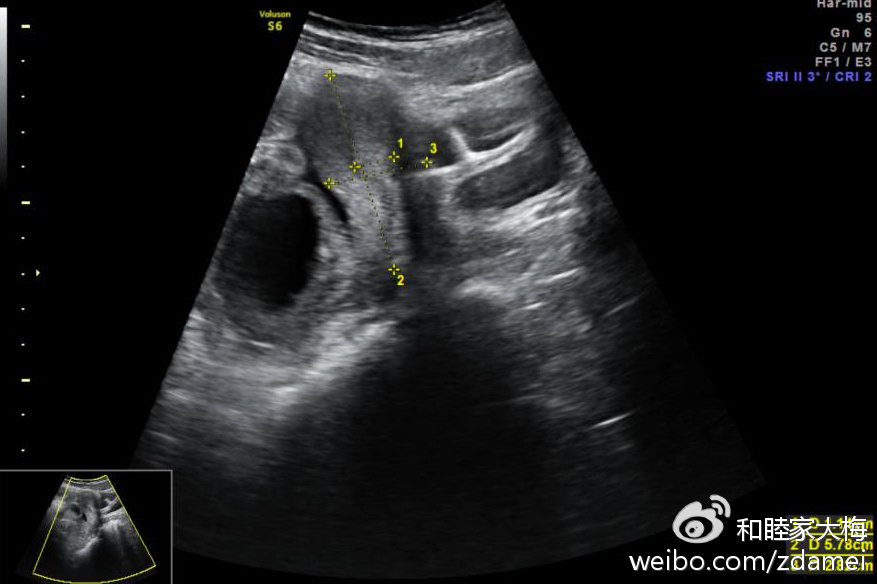

盆腔包块一例(术后诊断:右输卵管系膜囊肿)

盆腔包块一例术后诊断右输卵管系膜囊肿